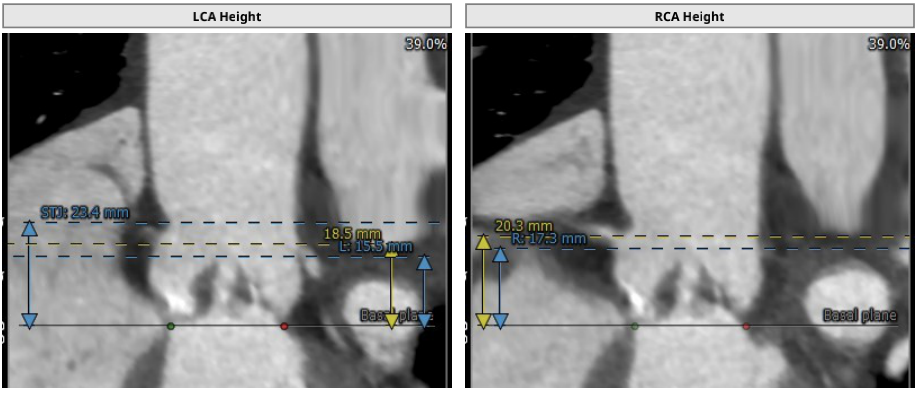

术前CT结果显示,主动脉瓣口面积498.2mm²,瓣环平均直径25.4mm,瓣环周长80.43mm;LVOT面积523.8 mm²,LVOT平均直径25.8mm;升主动脉平均直径29.2 mm;心夹角44°;左冠开口高度15.5mm、右冠开口高度17.3mm。

患者Type 0型二叶瓣,重度钙化,冠脉三支病变,左右冠脉开口高度15.5mm/17.3mm,左主干开口内侧较低,手术策略选择需综合考虑以下因素: